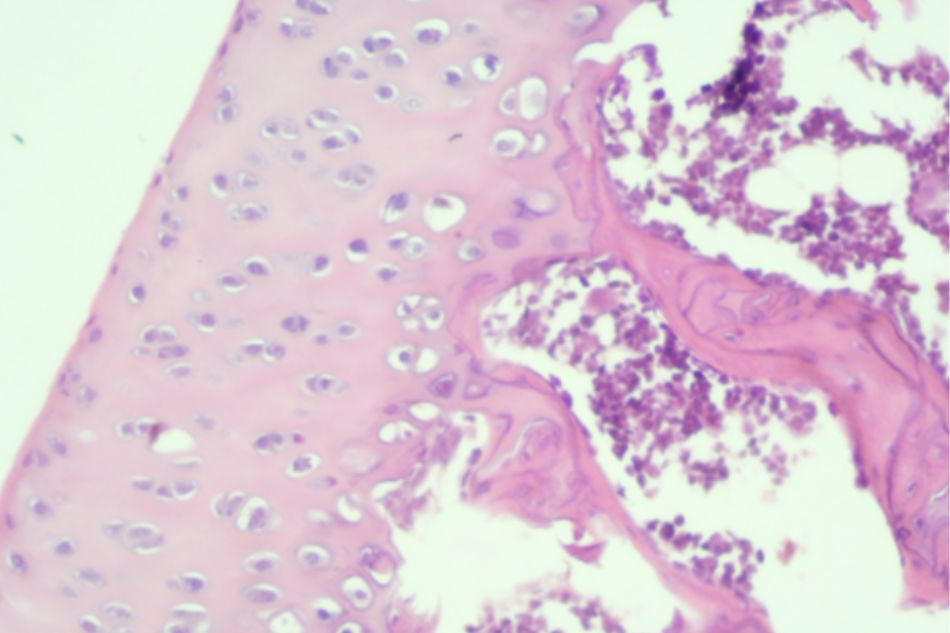

Figure 2.2. Knee joint sample in Group I (rat no.1)

Normal structure of knee joint

Figure 2.3. Knee joint sample in Group I (rat no.2)